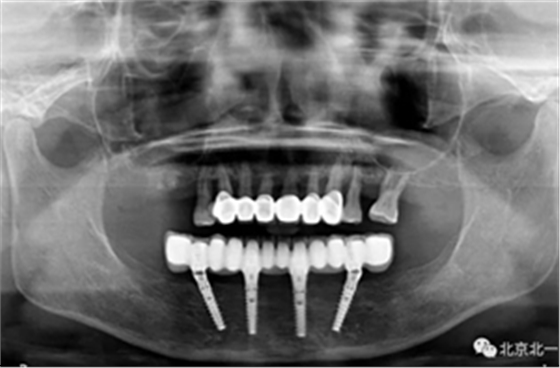

圖十七:拍X片確認無誤差

圖十八:口內(nèi)試戴鈦支架

圖十九:永久修復(fù)完成

圖二十:永久修復(fù)咬合關(guān)系